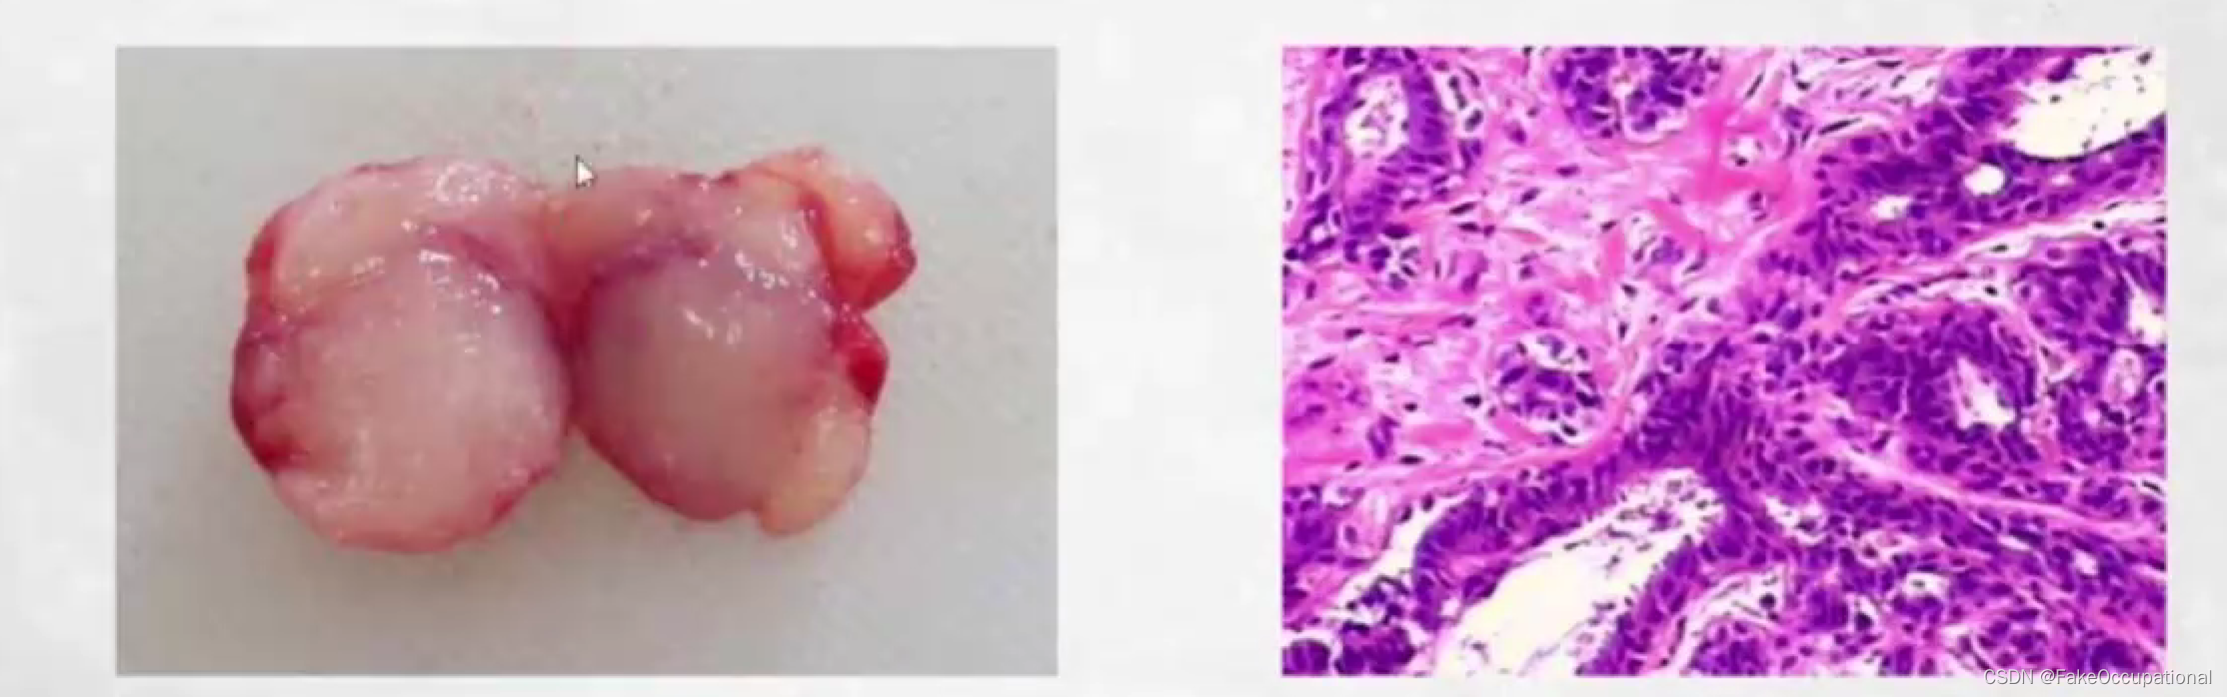

乳腺导管内乳头状瘤